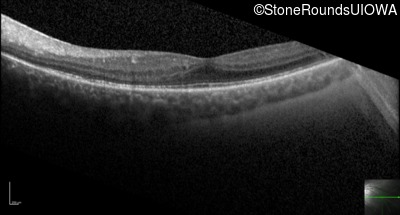

Optical Coherence Tomography - Left - 20/32 -1

Exemplar / OCT Stack

Optical Coherence Tomography - Left - 20/32 +1